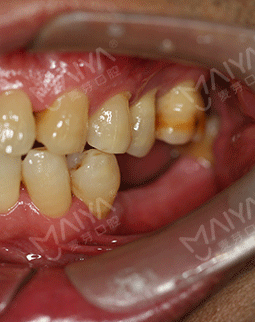

由于职业原因,特别爱好摄影和旅游。去年年底到今年6月,和朋友们分别去了南极和北极,我把这次南北极之旅称之为“南征北战”。尽管今年已经58岁了,热爱冒险又健谈的我和同龄人相比起来却像一个40多岁的人。但由于年轻时对口腔保护意识的薄弱,导致了现在口内5颗牙缺失,大家都想不到吧?别人是缺前牙,我是缺大牙,这大牙可是咀嚼食物的主要牙齿,所以我很多时候吃饭都是囫囵吞枣,对饮食生活造成了相当大的困扰。吃东西费劲,很多时候朋友邀约出去聚会,却只能眼睁睁的看着大家享受美食。随着年龄的增长,缺牙造成的营养吸收不均衡,在饮食和身体健康上带给我的是双重困扰。有人劝我镶牙,但活动牙我看不上,固定牙又不适合伤害健康的牙齿,思前想后,还是决定种牙。

2017年7月 口腔保健意识差,导致我口内5颗牙缺失

由于职业原因,特别爱好摄影和旅游。去年年底到今年6月,和朋友们分别去了南极和北极,我把这次南北极之旅称之为“南征北战”。尽管今年已经58岁了,热爱冒险又健谈的我和同龄人相比起来却像一个40多岁的人。但由于年轻时对口腔保护意识的薄弱,导致了现在口内5颗牙缺失,对饮食生活造成了相当大的困扰。吃东西费劲,很多时候朋友邀约出去聚会,却只能眼睁睁的看着大家享受美食。随着年龄的增长,缺牙造成的营养吸收不均衡,在饮食和身体健康上带给我的是双重困扰。

我虽然走遍大江南北,也看遍了大江南北的风光。这本是羡煞旁人的事,但对我来说,却有许多遗憾。20年前牙齿就开始脱落了,但当时科学、技术都没有达到现在的标准,自己也没有太在意,如今随着生活品质的提升,科学、技术的提高,对恢复牙齿的需求也变得越来越迫切。